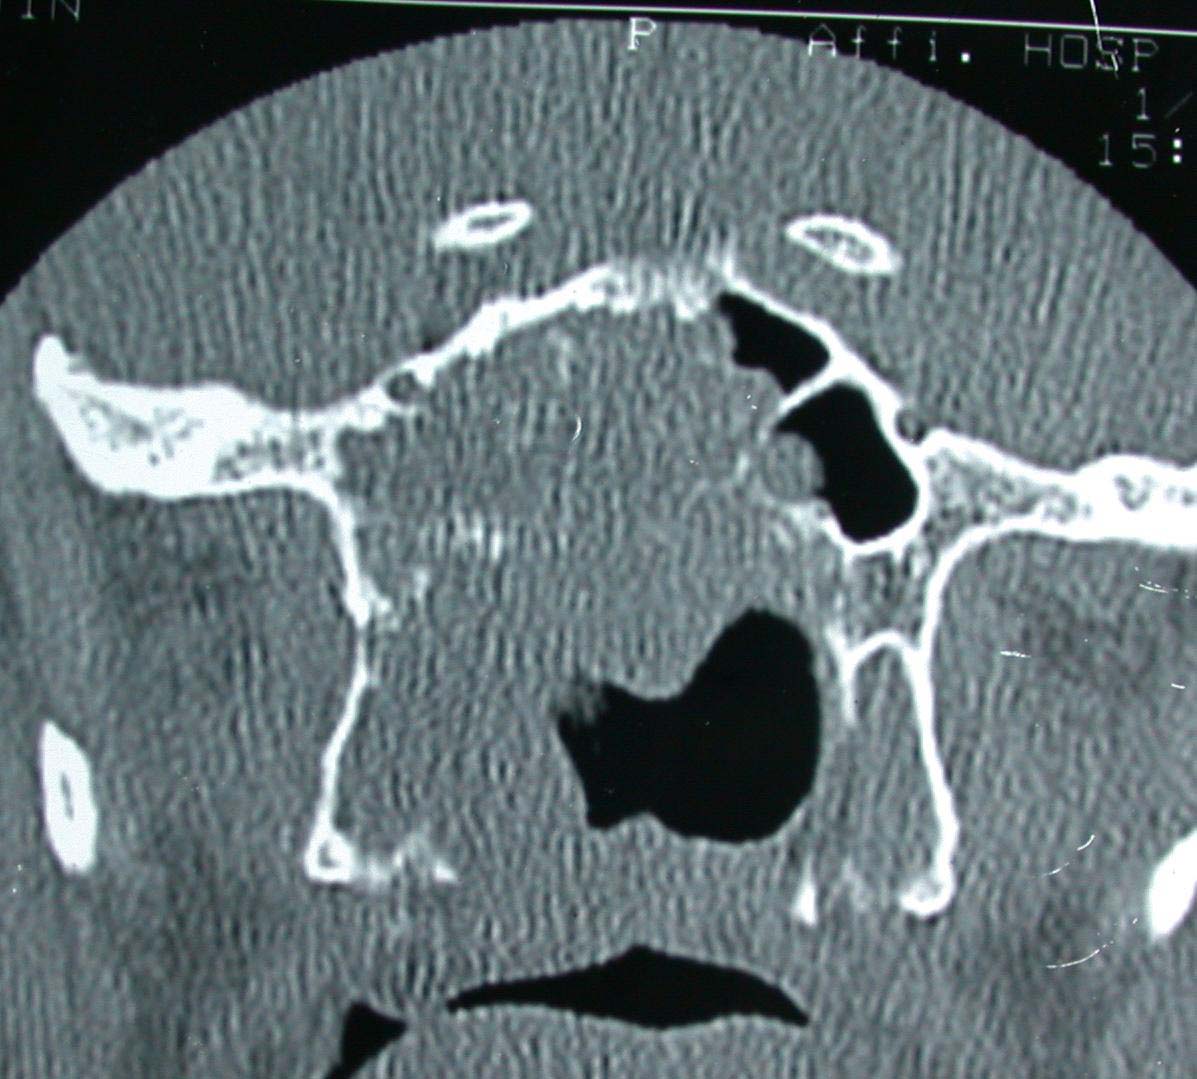

术前